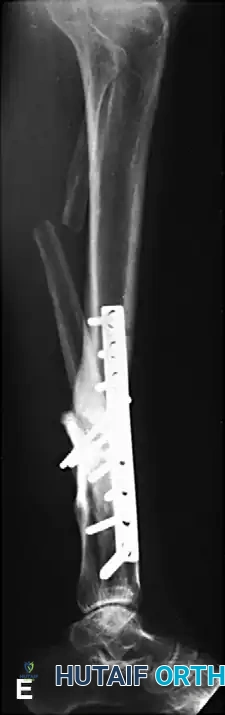

Image

Postoperative AP and Lateral radiographs demonstrating solid tibial union with restoration of normal mechanical alignment. An asymptomatic nonunion of the fibular osteotomy persists, which is a common and clinically benign finding.